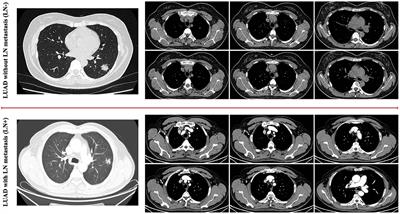

Published on 10 Feb 2022

in Precision Medicine

Published on 26 Oct 2021

in Cancer Imaging and Image-directed Interventions